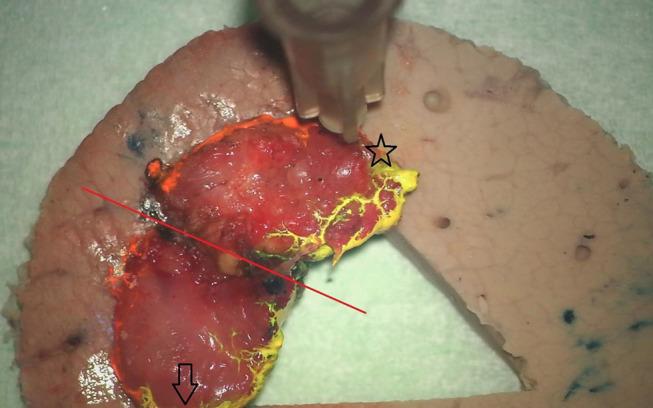

The value of margin status after TLM for glottic cancer is debatable, due to difficulties in specimen orientation and margin analysis. Purpose of this study was the prospective evaluation of feasibility of a new standardized technique of oriented fixation of the TLM specimen and identification of the added value on tissue processing and margin status reporting. Patients with suspicious glottic lesions undergoing TLM were included. After resection, the specimen margins were inked in the OR using different colors. Subsequently, the specimens were fixed on a pig liver carrier and sent for further processing, accompanied with photographs of the larynx pre-TLM and of the mounted specimen. Feasibility was assessed by registration of duration of specimen preparation in the OR and the lab and by procedure-specific questionnaires. Objective evaluation included assessment of margin status and proportion of evaluable margins. Chi square tests were used to make comparisons of proportions. One hundred and four consecutive patients were included between May 2016 and September 2019. TLM was performed in a primary and salvage setting in 89.4 and 10.6% of patients, respectively. Mean duration of intraoperative specimen preparation was 5.1 min (SD 2.6 min). No difficulties in orientation nor fixation during intraoperative preparation were reported in 87.5 and 88.2%, respectively. Specimen orientation was judged by the pathologist as very adequate in 89.4%, with the accompanying photographs considered helpful for orientation and processing in 84.6%. Substantial difficulties in further lab processing and pathologic examination were identified in 17.7%. Deep margin evaluability was very high (98.0%) and significantly higher than the evaluability of superficial mucosal margins. Compared to our previous series published by our group ( = 142), deep margin evaluability significantly rose from 62.7 to 98.0% ( < 0.001) and true positive rate of the deep margins increased from 0 to 44.4% ( = 0.002). The new and standardized technique of oriented fixation of TLM specimens on a pig liver carrier proves feasible both in the OR and lab setting and results in high margin evaluability rates, especially for the deep margin, as well as a decreased rate of false positive deep margins when compared to a historical TLM cohort.

由于标本定位和切缘分析存在困难,对于声门癌患者而言,在激光显微手术(TLM)后切缘状态的价值存在争议。本研究的目的是前瞻性评估一种新的标准化技术,即对TLM标本进行定向固定的可行性,并确定其在组织处理和切缘状态报告方面的附加价值。纳入接受TLM的可疑声门病变患者。切除后,在手术室使用不同颜色对标本切缘进行标记。随后,将标本固定在猪肝载体上并送去进一步处理,同时附上TLM术前喉部及固定后标本的照片。通过记录手术室和实验室中标本制备的持续时间以及特定程序问卷来评估可行性。客观评估包括切缘状态评估和可评估切缘的比例。使用卡方检验进行比例比较。2016年5月至2019年9月期间连续纳入104例患者。分别在89.4%和10.6%的患者中,TLM用于初次治疗和挽救性治疗。术中标本制备的平均持续时间为5.1分钟(标准差2.6分钟)。分别有87.5%和88.2%的患者报告术中制备过程中在定位和固定方面没有困难。病理学家判定标本定位非常合适的比例为89.4%,84.6%的人认为附带的照片有助于定位和处理。17.7%的患者在进一步的实验室处理和病理检查中发现存在重大困难。深部切缘的可评估性非常高(98.0%),且显著高于浅表黏膜切缘的可评估性。与我们团队之前发表的系列研究(n = 142)相比,深部切缘的可评估性从62.7%显著提高到98.0%(P < 0.001),深部切缘的真阳性率从0增加到44.4%(P = 0.002)。将TLM标本在猪肝载体上进行定向固定的新标准化技术在手术室和实验室环境中均被证明是可行的,并且切缘可评估率很高,尤其是深部切缘,与历史TLM队列相比,深部切缘假阳性率降低。